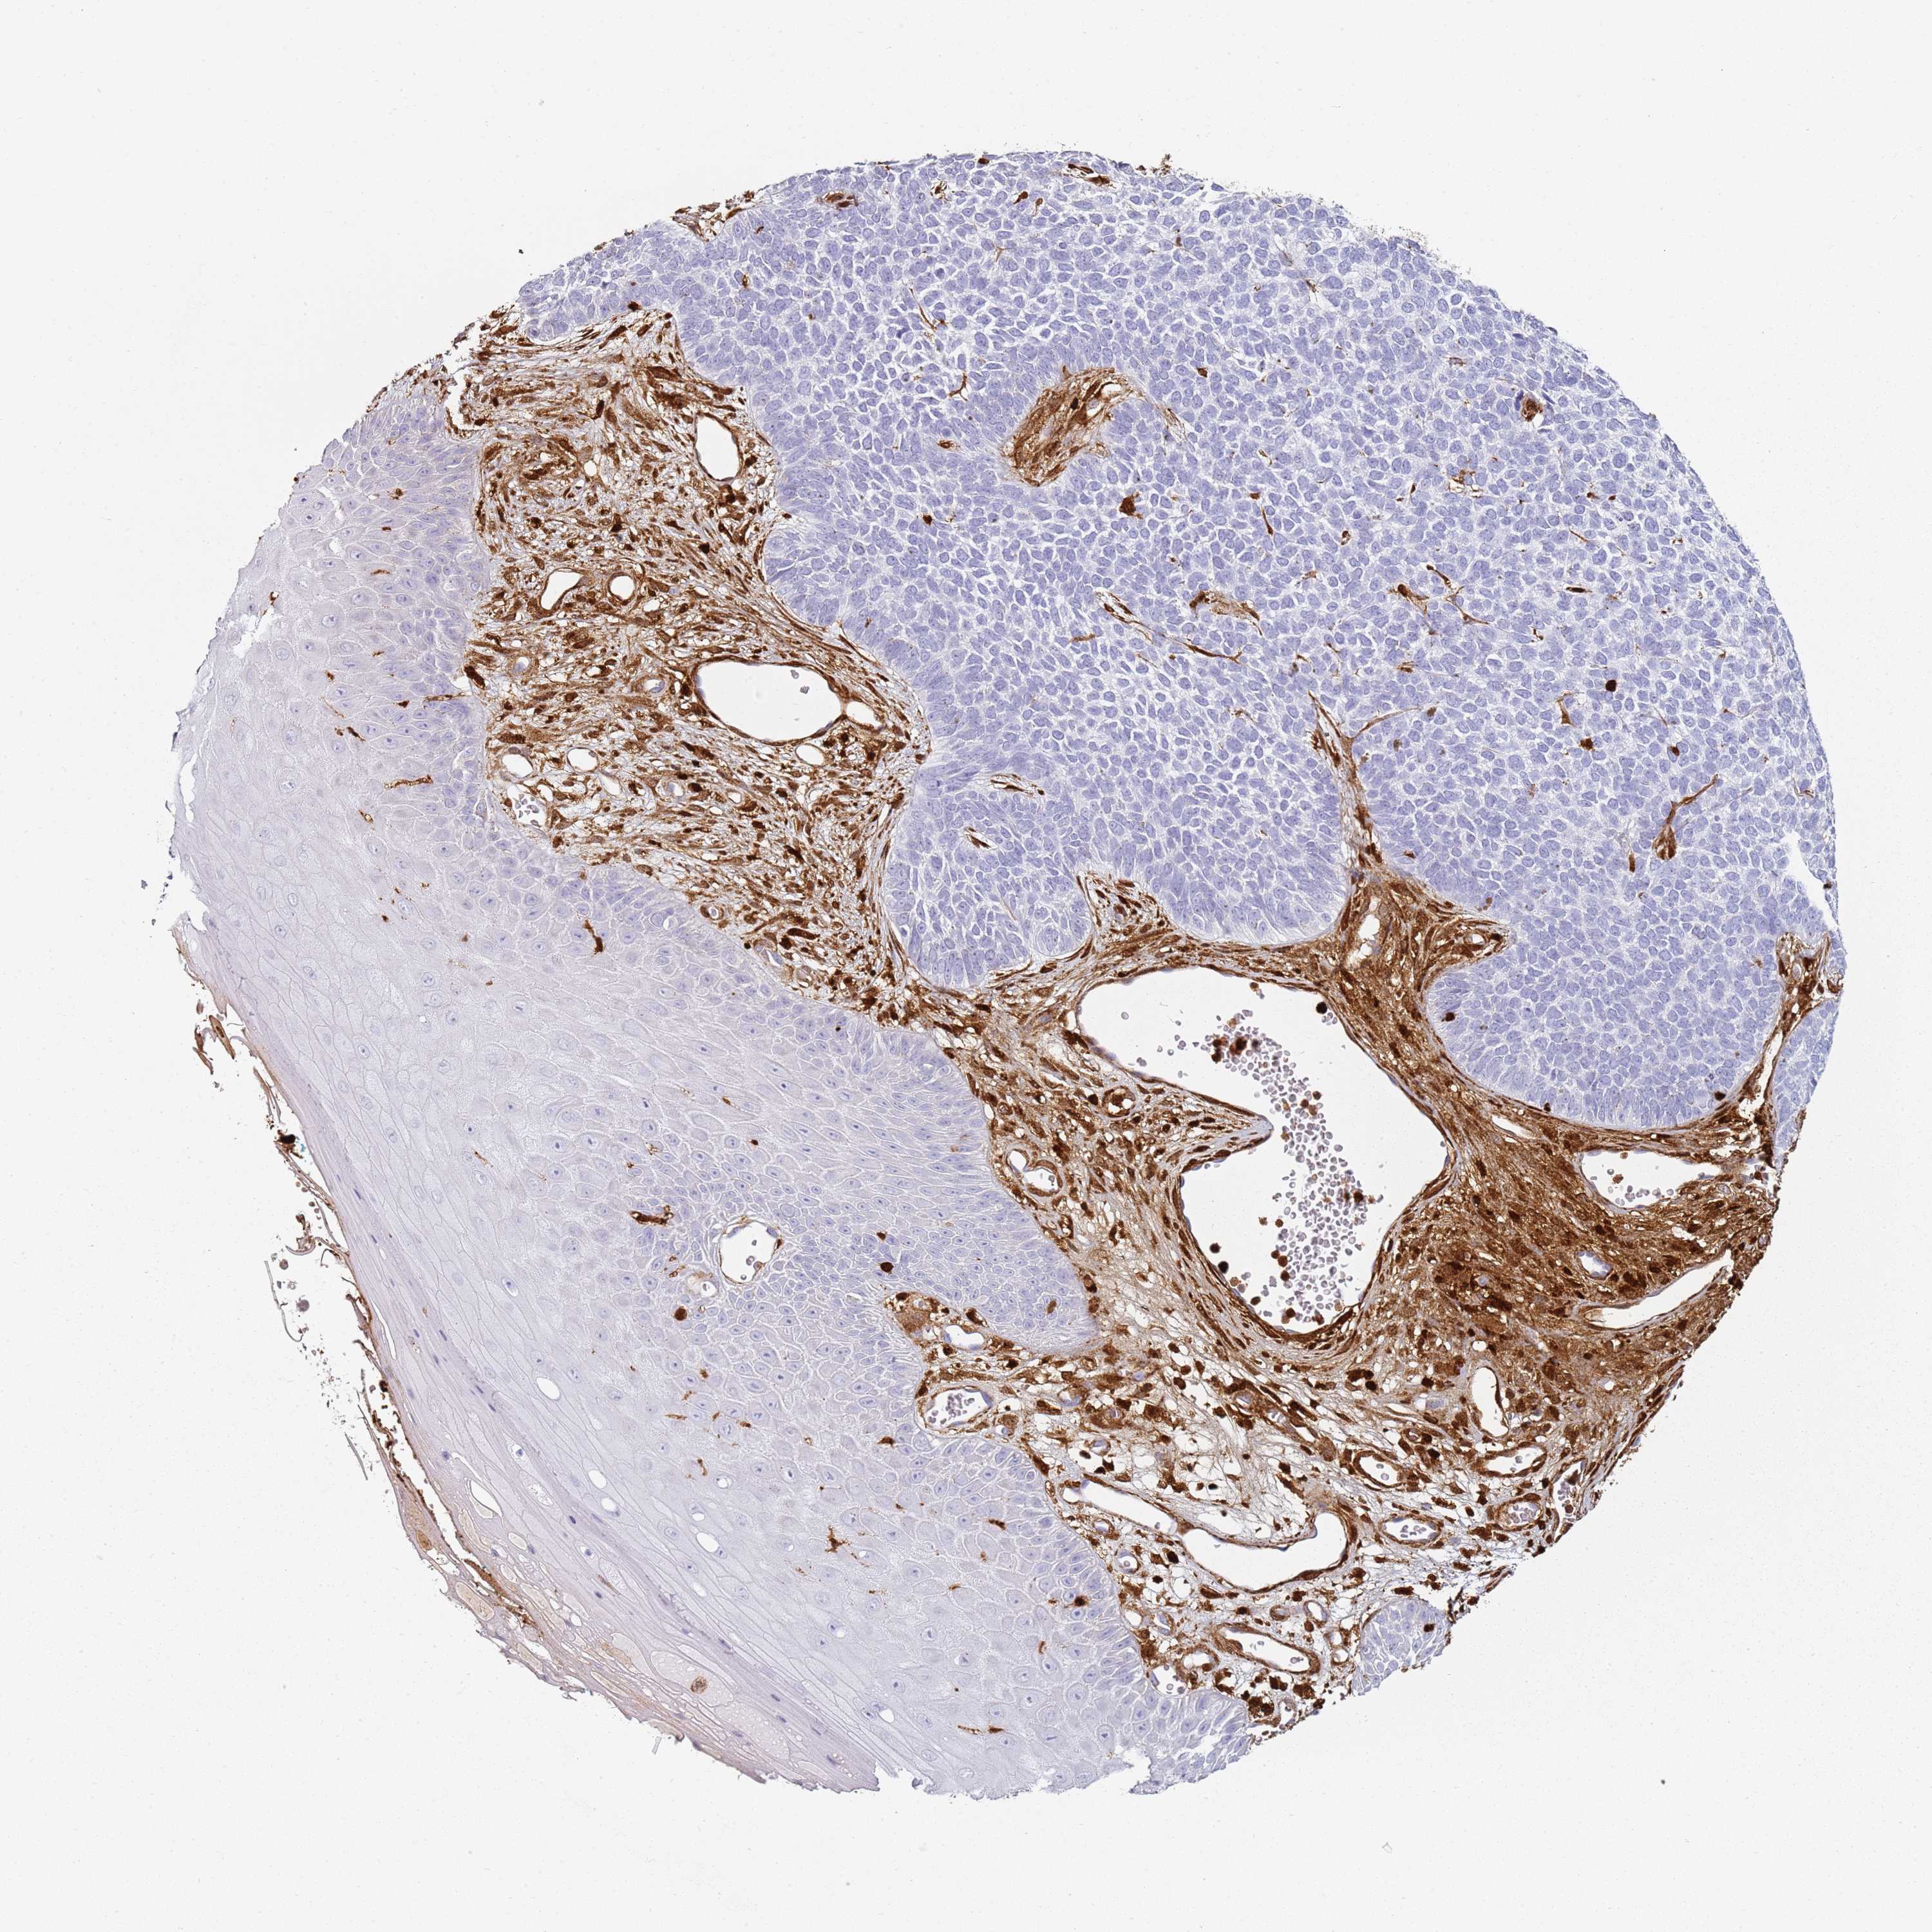

CANCER SKIN CANCER Show tissue menu

Basal cell and squamous cell cancer

SKIN CANCER - Protein expressioni

A mouse-over function shows sample information and annotation data. Click on an image to view it in a full screen mode. Samples can be filtered based on level of antibody staining by selecting one or several of the following categories: high, medium, low and not detected. The assay and annotation is described here.

Each image is clickable and will lead to virtual microscopy that enables deeper exploration of all samples and also displays staining intensity scores, fraction scores and subcellular localization as well as patient and tissue information for each sample.

HPA007973

CAB002618

CAB027387

CAB058698

CAB068227

CAB068228

Basal cell carcinoma

Squamous cell carcinoma, NOS

Squamous cell carcinoma, metastatic, NOS